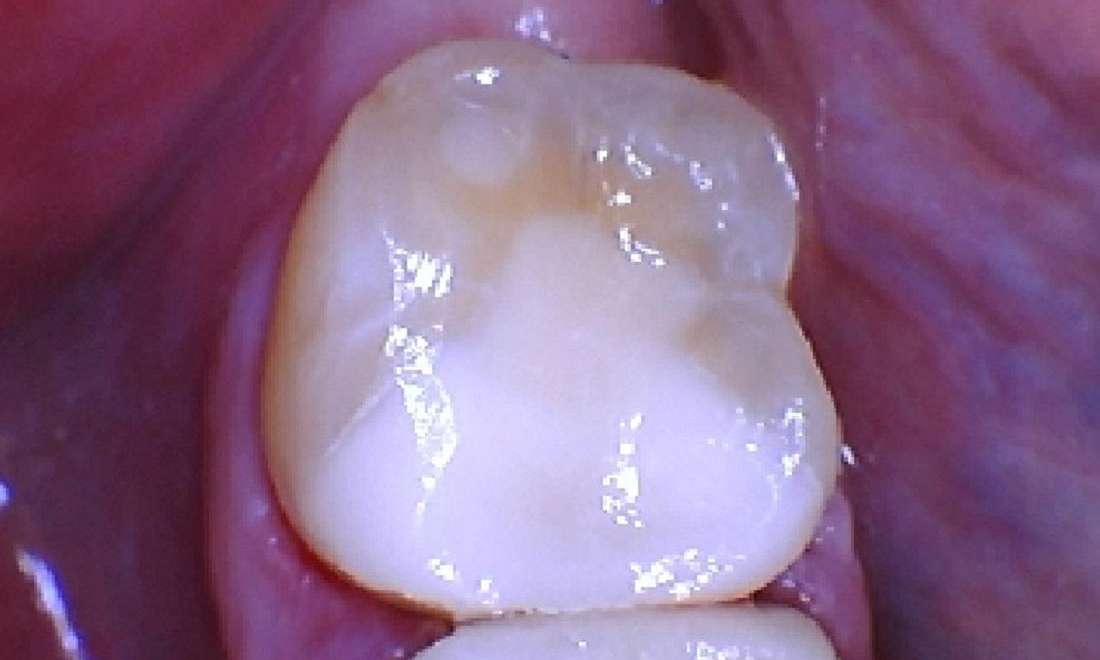

Broken Tooth Repaired White Filling

The patient came to our office with a broken tooth, which was quite concerning. Upon examination, we noticed that the old filling had deteriorated, leaving the tooth exposed and susceptible to further decay. The before photo highlights the damage, showing the cracked surface and the wear around the filling.